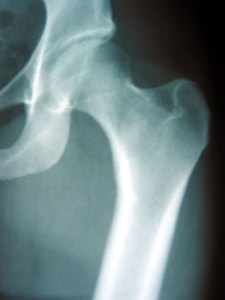

My hip flare up, that was just this little thing, that was supposed to calm down after the cortisone injection….has become a complicated mess.

I had my hip injection on September 11th. We got Kiki that evening. It was an exciting day. I expected to be sore that night. I expected to possibly be sore the next day, but would probably feel better….and continue to get better. That didn’t happen.

I’m not sure if the shot did anything. I don’t think so. However. on the night of September the 12th, I got up and went to the bathroom. I started to sit on the toilet and lost my footing and fell, hard, onto the seat. My elbow hit the back of the toilet where I keep a box with things in it and I got a nice little scrape on it. The big hurt was my hip. OW! The pain shot through me, from the top of my buttock, along my side down through my knee….I was in PAIN! I have been in constant pain in this areas since that night. The pain ebbs and flows, but never gets better than a 6, and if often hovering around an 8. I had Stuart give me a Toradol injection. This really helped. Toradol is a nonsteroidal anti-inflammatory drug. (I can’t take NSAIDs by mouth because they tear up my stomach, but I can have these injections occasionally.) Since this worked to take most of the pain away I was sure I hadn’t broken anything. I was also hoping the cortisone shot would kick in and help. So I waited….

The cortisone didn’t help. I went back to the doctor on the 18th. She was disheartened. She suspects that my pain may be coming from my spine, and maybe also from my hip. She set up a CT scan with contrast dye, and she wants me to see a spine specialist, and a more specialized hip doctor. (she is actually a PA in the office, she wants me to see a specific doctor in the practice). I will have the CT scan on Friday. (I was originally supposed to have the CT scan today, but I didn’t sleep at all last night and I can’t control the Meniere’s vertigo today, and since I could get in closer to my doctor’s appointment I decided to change the appointment.) I see the hip specialist on October 1st, and I’m not sure when I see the spine doctor yet, I haven’t heard from their office yet.